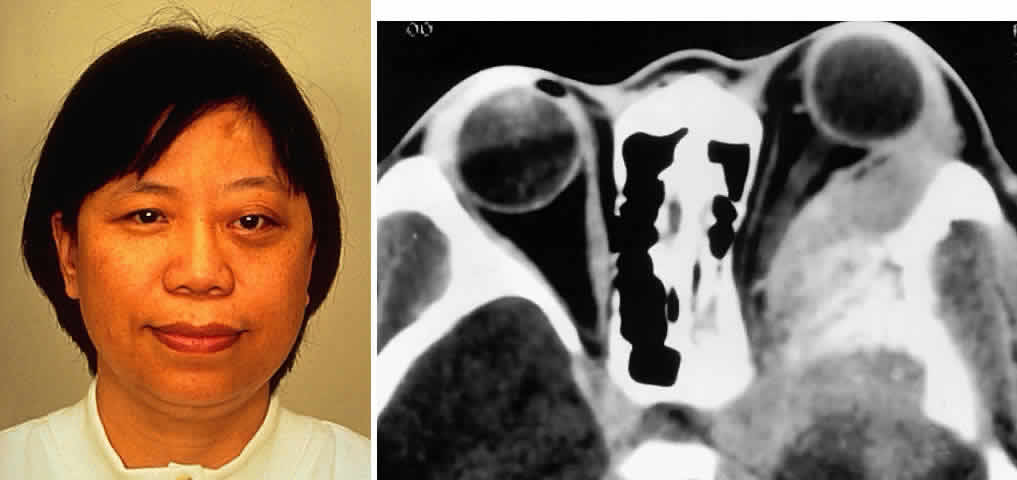

Fig. 2. A 32-year-old woman presented with a 1-month history of sinus congestion and nasal obstruction unresponsive to antibiotics. In the 1 week preceding the initial exam, the right eye became progressively more prominent and showed tearing and redness. On examination, there was mild edema of the lower lid and dysesthesia in the distribution of cranial nerve V2, and the globe was displaced 6 mm laterally and 5 mm anteriorly. There was mild limitation of abduction, chemosis, and nasal choroidal folds. An axial CT scan revealed a diffuse, destructive soft tissue mass centered in the superior nasal passage and ethmoid sinuses extending into the right orbit in contiguity with the medial rectus (A). On enhanced coronal view, the tumor was noted to involve the right maxillary antrum and to extend superiorly into the anterior cranial fossa (B). Biopsy of the sinus (C) revealed an alveolar-type rhabdomyosarcoma (muscle stain, × 320).

Fig. 3. A 73-year-old man presented with a 2-year history of infraorbital numbness and burning sensation, which had progressed to include the supraorbital region, forehead, and lower face during the past 6 months. He had been treated with radiotherapy for prostate carcinoma 7 months before orbital presentation. Examination was significant for proptosis of 2 mm and dysesthesia, including corneal numbness, in all three divisions of cranial nerve V. CT scan revealed a soft tissue mass in the inferior orbit contiguous with the inferior rectus muscle (A). The lesion extended through the infraorbital canal to involve the pterygopalatine fossa and was associated with soft tissue hanging into the upper portion of the maxillary sinus. An axial CT scan-guided aspiration biopsy was performed (B) and revealed squamous cell carcinoma. Groups of cohesive malignant squamous epithelial cells (C) were noted to have pleomorphic nuclei and abundant eosinophilic to orange cytoplasm, with no features of mucinous differentiation (H & E, × 320). (C from White VA, Rootman J: Orbital pathology. In Albert DM, Jakobiec FA (eds): Principles and Practice of Ophthalmology, Vol 4, p 2342. Philadelphia, WB Saunders, 1994.)